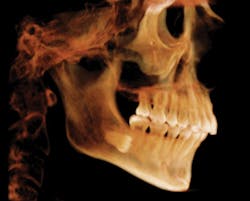

These are typical 3-D images created with a CBCT scan. These images can be moved in any direction needed for a better view of what patients need to see. It is also possible to remove layers along the axial, coronal, and sagittal planes to enhance views.

Cone-beam computed tomography, commonly referred to as CBCT, is 3-D imaging using cone-beam scanners that produce -layers of images to help diagnose patients. The 3-D images provide information that helps with more accurate diagnosis and treatment planning, and it eliminates the guesswork of traditional 2-D images.